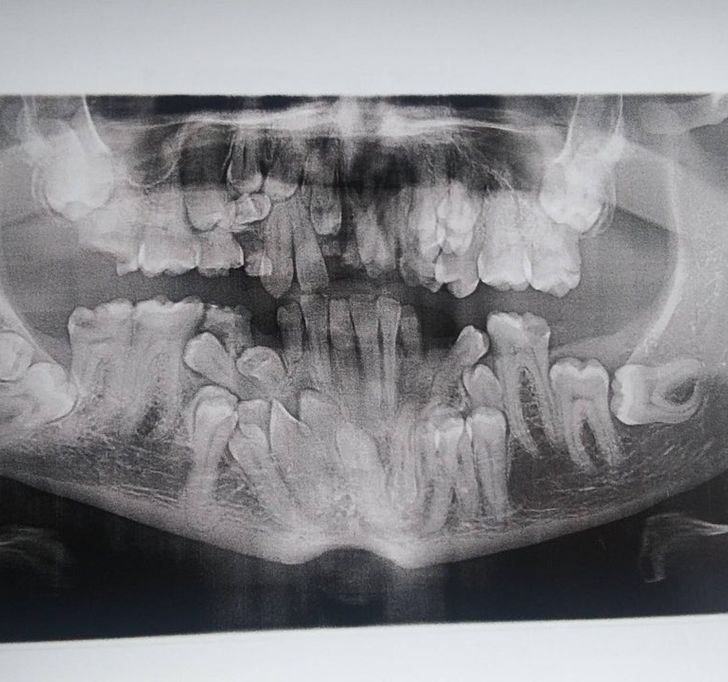

19. „Ritka betegségem van, az úgynevezett cleidocranial dysostosis. Ma kaptam meg az első fogászati röntgenfelvételemet, és rengeteg fogam van. “